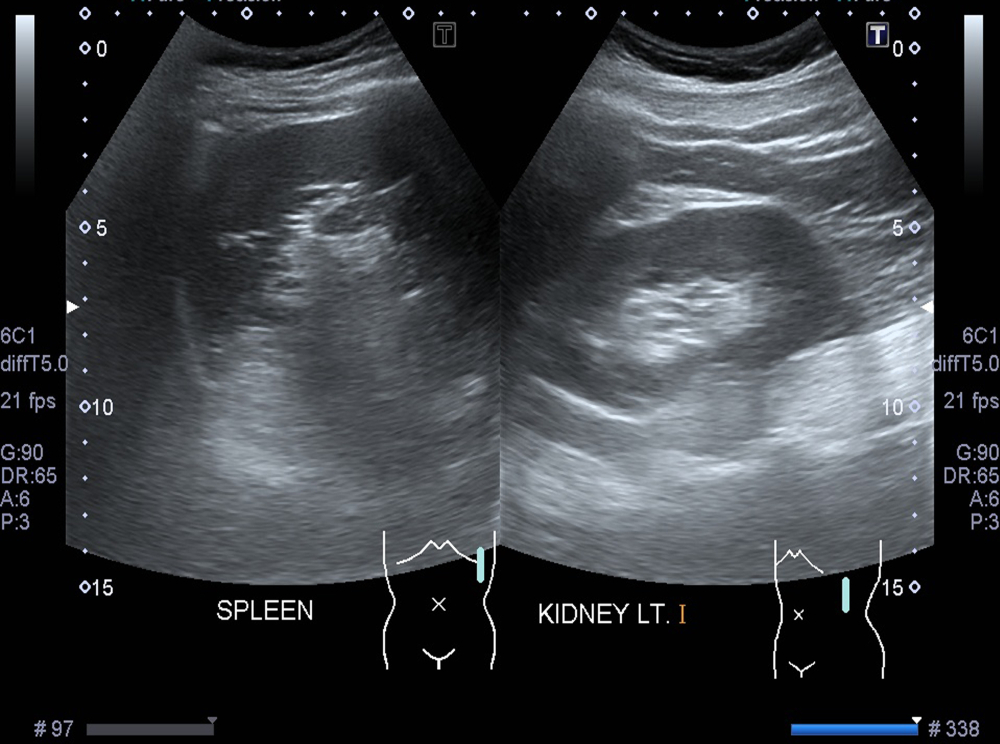

Фотогалерея

Оборудование УЗИ